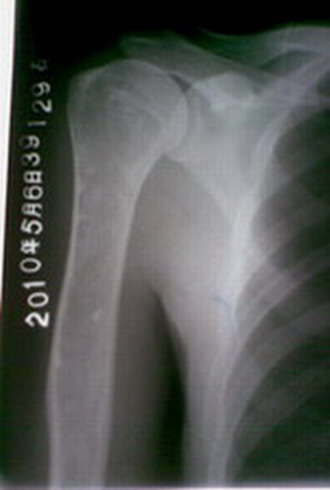

以下是引用zsl6918在2010-5-8 7:25:00的发言:[br]楼主是否怀疑肱骨干中上端的骨密度不均匀?

以下是引用随光逐影在2010-5-8 9:31:00的发言:[br]甲状旁腺机能亢进所致骨骼改变?

以下是引用子期在2010-5-8 6:24:00的发言:[br]好象未见明显异常,不知楼主怀疑什 么?[br]渠县人民医院的技术那么强,应该能搞定的。